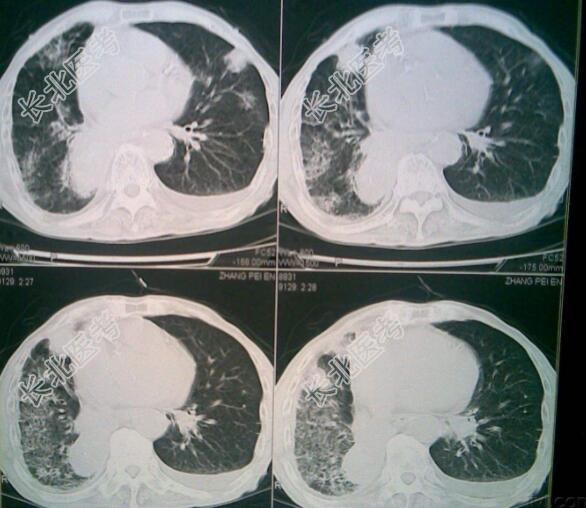

男性,68岁。发现肺癌3月余,憋喘伴咳嗽咳痰4天。现病史:患者3月前无明显诱因反复出现刺激性干咳,伴有发作性呛咳气急,当时无痰中带血,自行服药症状不缓解,在当地医院查胸部CT示右肺占位,其后去徐州四院就诊,予以肺部增强CT及穿刺活检病理示"肺鳞癌",联系外科手术风险大,与家属沟通后排除化疗禁忌行GP(吉西他滨+奈达铂)化疗一次,近期在我院行第二次化疗,当时症状缓解出院;4日前劳累后再次出现咳嗽咳痰,痰粘稠难咳,阵发性胸闷心慌,无胸痛不适,无发热畏寒,无腹痛腹胀腹泻,无呕血黑便,在家自服药(具体不详),效果欠佳,今为求系统治疗及行第三次化疗特来我院收入我科,发病来,患者神清精神欠佳,活动后胸闷心慌,咳嗽偶有痰中带血,无恶心呕吐,无头晕头痛,二便尚正常。既往史:既往体健无特殊病史查体:T:36.5℃,P:80次/分,R:20次/分,BP:135/80/mmHg。意识清晰,言语流利,体型偏瘦,步入病房,查体尚合作。全身皮肤黏膜无黄染,无皮下出血点,浅表淋巴结未触及肿大及压痛;头颅无畸形,面纹对称,面部萎黄,耳鼻无异常分泌物,巩膜无黄染,结膜无充血,双瞳孔等大等圆,直径3.0mm,对光反射灵敏;口唇稍紫绀,伸舌居中,咽部无充血,扁桃体不大。颈软无抵抗,气管居中,甲状腺不大。胸廓对称无畸形,两肺呼吸音粗,可闻及少许湿啰音,心率80次/分,心律齐,各瓣膜听诊区未闻及明显杂音。腹软平坦,无包块,胃脘轻压痛无反跳痛,肝脾肋下未触及,莫氏征(-),麦氏点无压痛,移动性浊音(-),肠鸣音正常无亢进。脊柱四肢无畸形,活动可;四肢肌力5级,肌张力正常,生理反射存在,病理反射未引出。双下肢无水肿。辅助检查:心脏彩超未见异常;血生化基本正常,肺癌指标升高;胸部增强CT:右肺上叶肿块、右肺上叶尖段支气管闭塞、右肺门淋巴结肿大,考虑肺癌伴肺门淋巴结转移;肺穿刺病理:鳞癌;ECT:第三胸椎骨代谢活跃;出院前心电图:正常心电图;胸部CT:右侧气胸,右肺炎症,右上肺点状类软组织密度。